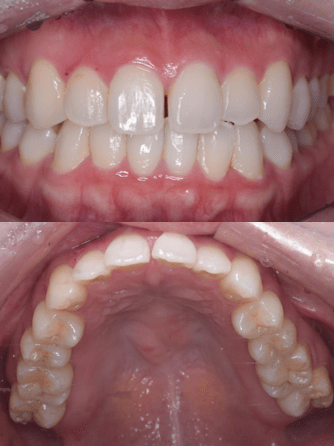

ビフォーアフター写真

治療前

治療後